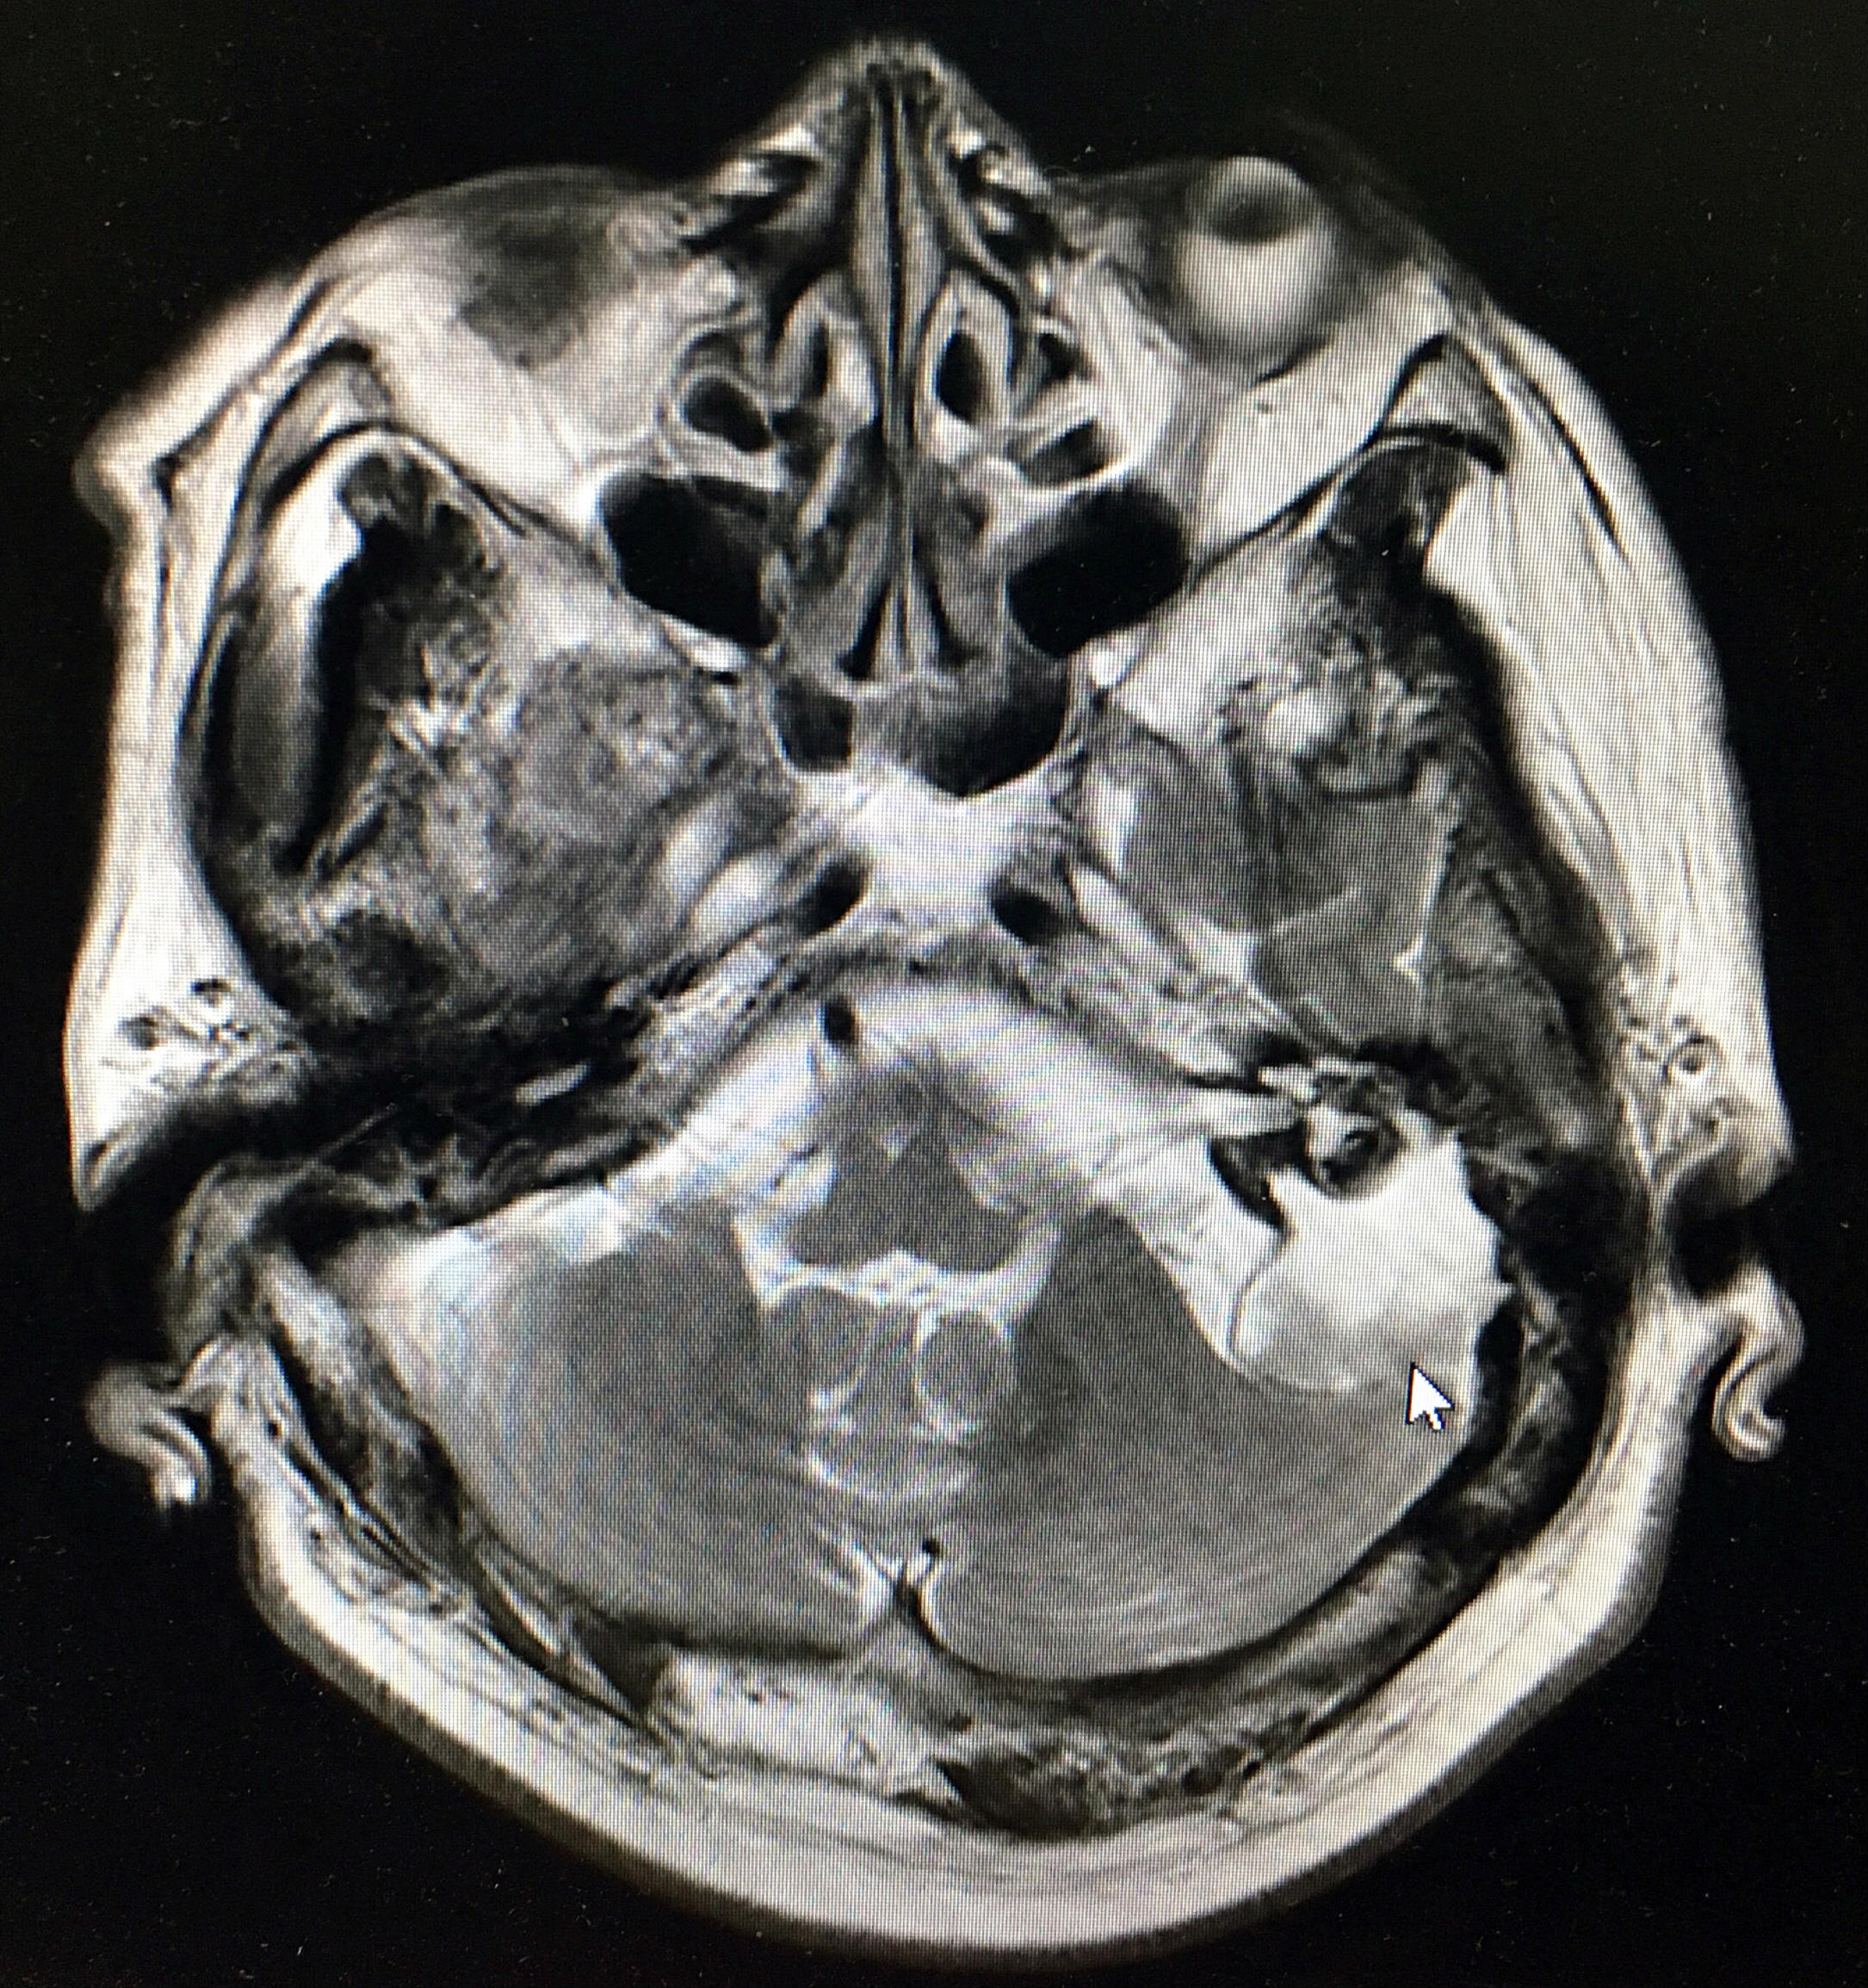

李大爷面瘫十余年,因有脑梗病史,多年来自己和家人都认为这面瘫是脑梗所致,没治,后因听力实在太差,影响交流,且出现耳痛,耳流血等症,才前来北京清华长庚医院就诊。不看病不知道,一看病吓一跳,伊海金主任门诊为李大爷拍了颞骨CT,竟考虑是颞骨岩部胆脂瘤。原来老先生的面瘫,罪魁祸首并非脑梗,而是耳病,这攒了多年的胆脂瘤已经破坏颅底,也就是说,耳朵的病,已经敲开了“邻居”脑子家的门,岩部胆脂瘤合并脑脊液耳漏。老爷子基础病多,全麻手术风险可想而知,伊海金主任及其耳科团队并未因此逃避,与患者共同面对,冒着风险为李大爷做了手术:全麻显微镜、耳内镜双镜联合进行了岩部次全切除术及脑脊液耳漏修补术,术后李大爷残余听力保存,多年的面瘫竟也有所恢复。

上图白色箭头所指为病变处